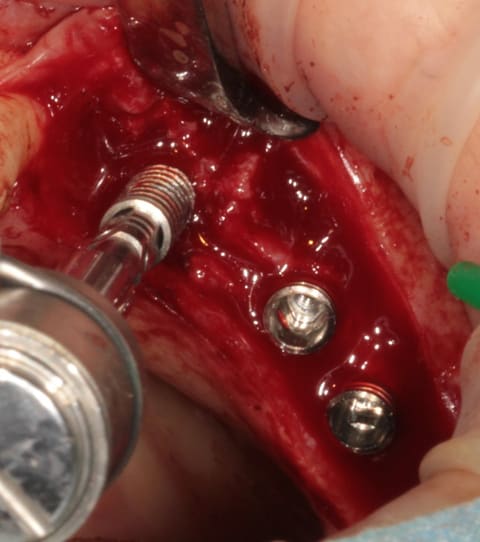

après les implants lisses coniques il faut passer aux lisses Axioms

donc Ostéotomes impactés pour mettre la corticale du sinus aux dimensions et pousser la membrane (et l'éponge)

en 25 pour le moment l'axiom lisse est de 3.4mm

puis les Axioms avec un 4 mm en 25

retouche de l'os avec le D1 (face plane)

contrôle de l'os vestibulaire (différents contraste pour juger de la "minceur" de l'os :-)))